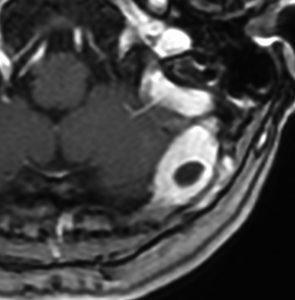

右中頭蓋窩から側頭下窩に抜けた,三叉神経鞘腫と誤診しやすいSFTです。dense collagen fiber の中に,核内空胞を有する異型細胞が密に増殖しています。MIB-1染色が10%程度と高いSFTでGrade IIb SFTと分類されるものです。

60代女性に偶然発見されたもので,小さな髄膜腫のようにみえ経過観察されました。5年間の経過で徐々に増大しました。

硬膜から発生してと頭蓋骨内に浸潤して骨破壊を伴いながら増殖する腫瘍でした。周囲の硬膜と頭蓋骨削除をして全摘出できました。グレード2のSFTです。このようなものは感全摘出で完治します。